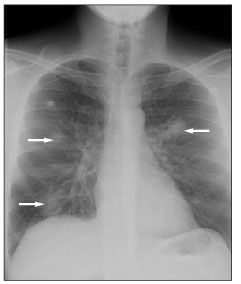

Figure 1.Chest radiograph demonstrating bilateral nodular densities (arrows).

A chest radiograph showed bilateral nodular densities (Figure 1), and a chest CT scan also demonstrated a nodular pneumonia (Figure 2). Because of a high suspicion for a fungal infection, the patient was empirically treated with voriconazole with cefepime added for bacterial coverage. He underwent bronchoscopy with bronchoalveolar lavage (BAL) on hospital day 3; viral cultures were initially positive for only cytomegalovirus (CMV). All other cultures, including fungal, bacterial, and mycobacterial cultures; acid-fast bacilli smear; direct fluorescent antibody testing for P jiroveci and Legionella; and BAL cytology yielded negative results. Multiple blood cultures were also negative, but his serum CMV DNA level, detected by polymerase chain reaction (PCR) assay, was 77,900 copies/mL.